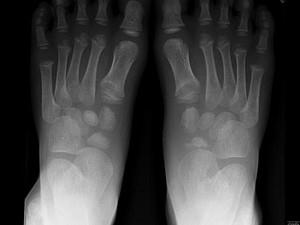

问题 男,5岁,足背肿痛,请结合图像,选出最可能的诊断 ( )

选项 A、软骨发育不全 B、剥脱性骨软骨炎 C、跗舟骨骨折 D、成骨不全 E、跗舟骨缺血坏死

答案 E